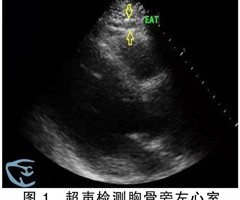

心外膜脂肪组织厚度与射血分数保留的心力衰竭的关系

摘要目的:探讨心外膜脂肪组织(EAT)厚度与射血分数保留的心力衰竭(HFpEF)的关系。方法:选取2021年12月—2022年4月就诊于沧州市中心医院心内科并诊断为HFpEF的62例病人作为研究组,选取同期于同一所医院体检中心进行健康体检者...